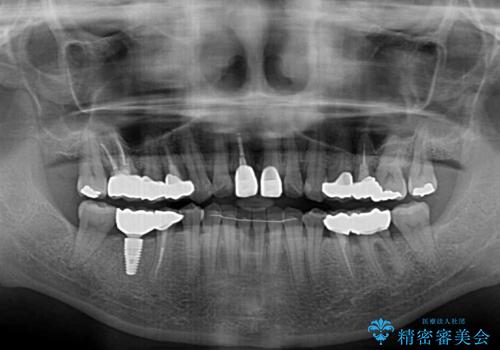

- 右下の欠損部の治療を希望して来院された患者様です。

部分矯正を行った後にインプラント埋入と手前の歯の根管治療を行い、その後補綴治療を行うこととしました。

治療途中より、上の歯や反対側の銀歯、上顎前歯の色合いや下顎前歯のデコボコが気になってきたため、全てを治療することとしました。